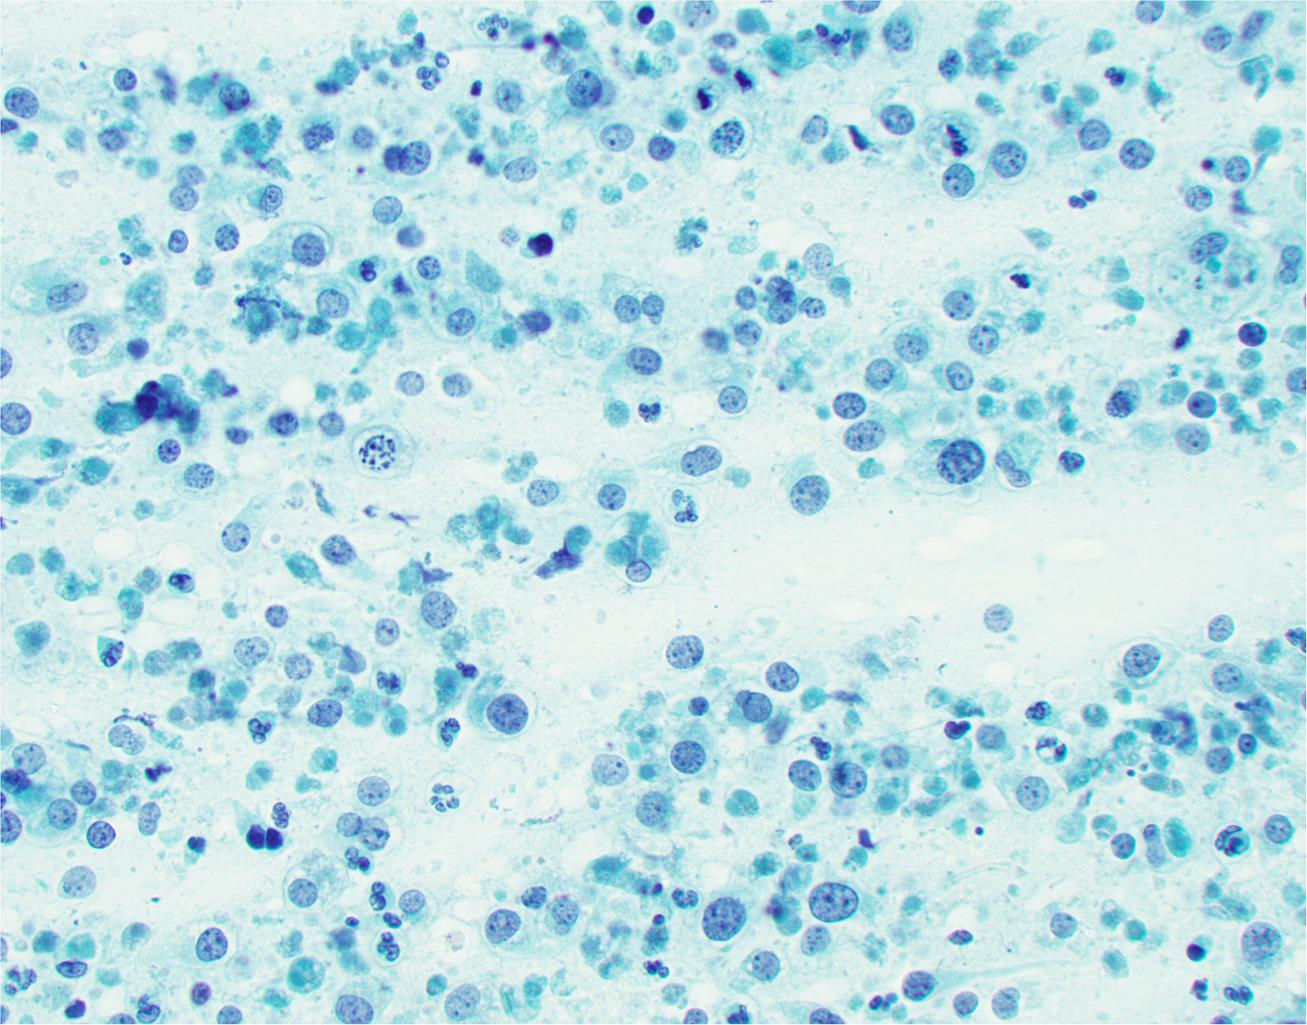

Thyroid lymphomas constitute about 5% of all thyroid malignancies.37 They are predominantly non-Hodgkin B-cell lymphomas (Fig. 14). The most common types are mucosa-associated lymphoid tissue (MALT) marginal zone lymphomas and diffuse large B cell lymphomas.37,38 Chronic lymphocytic (Hashimoto) thyroiditis is a risk factor for primary thyroid lymphomas reported in an average of 80% of primary thyroid lymphomas. FNA aspirates from lymphomas are often markedly cellular, consisting of numerous lymphocytes. Three patterns of thyroid lymphoma have been reported:39 1) a mixture of small and large lymphocytes, 2) a monotonous population of large lymphocytes, and 3) a monomorphous population of small lymphocytes. The first and third patterns can be seen in Hashimoto thyroiditis without oncocytic, follicular, and plasma cells. Like elsewhere in the body, immunophenotyping studies by immunohistochemistry and flow cytometry are essential for the diagnosis of lymphomas of the thyroid.

Fig. 14  Cytologic features of other rare tumors of the thyroid.

(a) Lymphoma showing mixed small and intermediate size lymphocytes (smear, Pap stain). (b) Metastatic renal cell carcinoma with vacuolated cytoplasm, round nuclei, and large prominent nucleoli (smear, Diff-Quik stain).